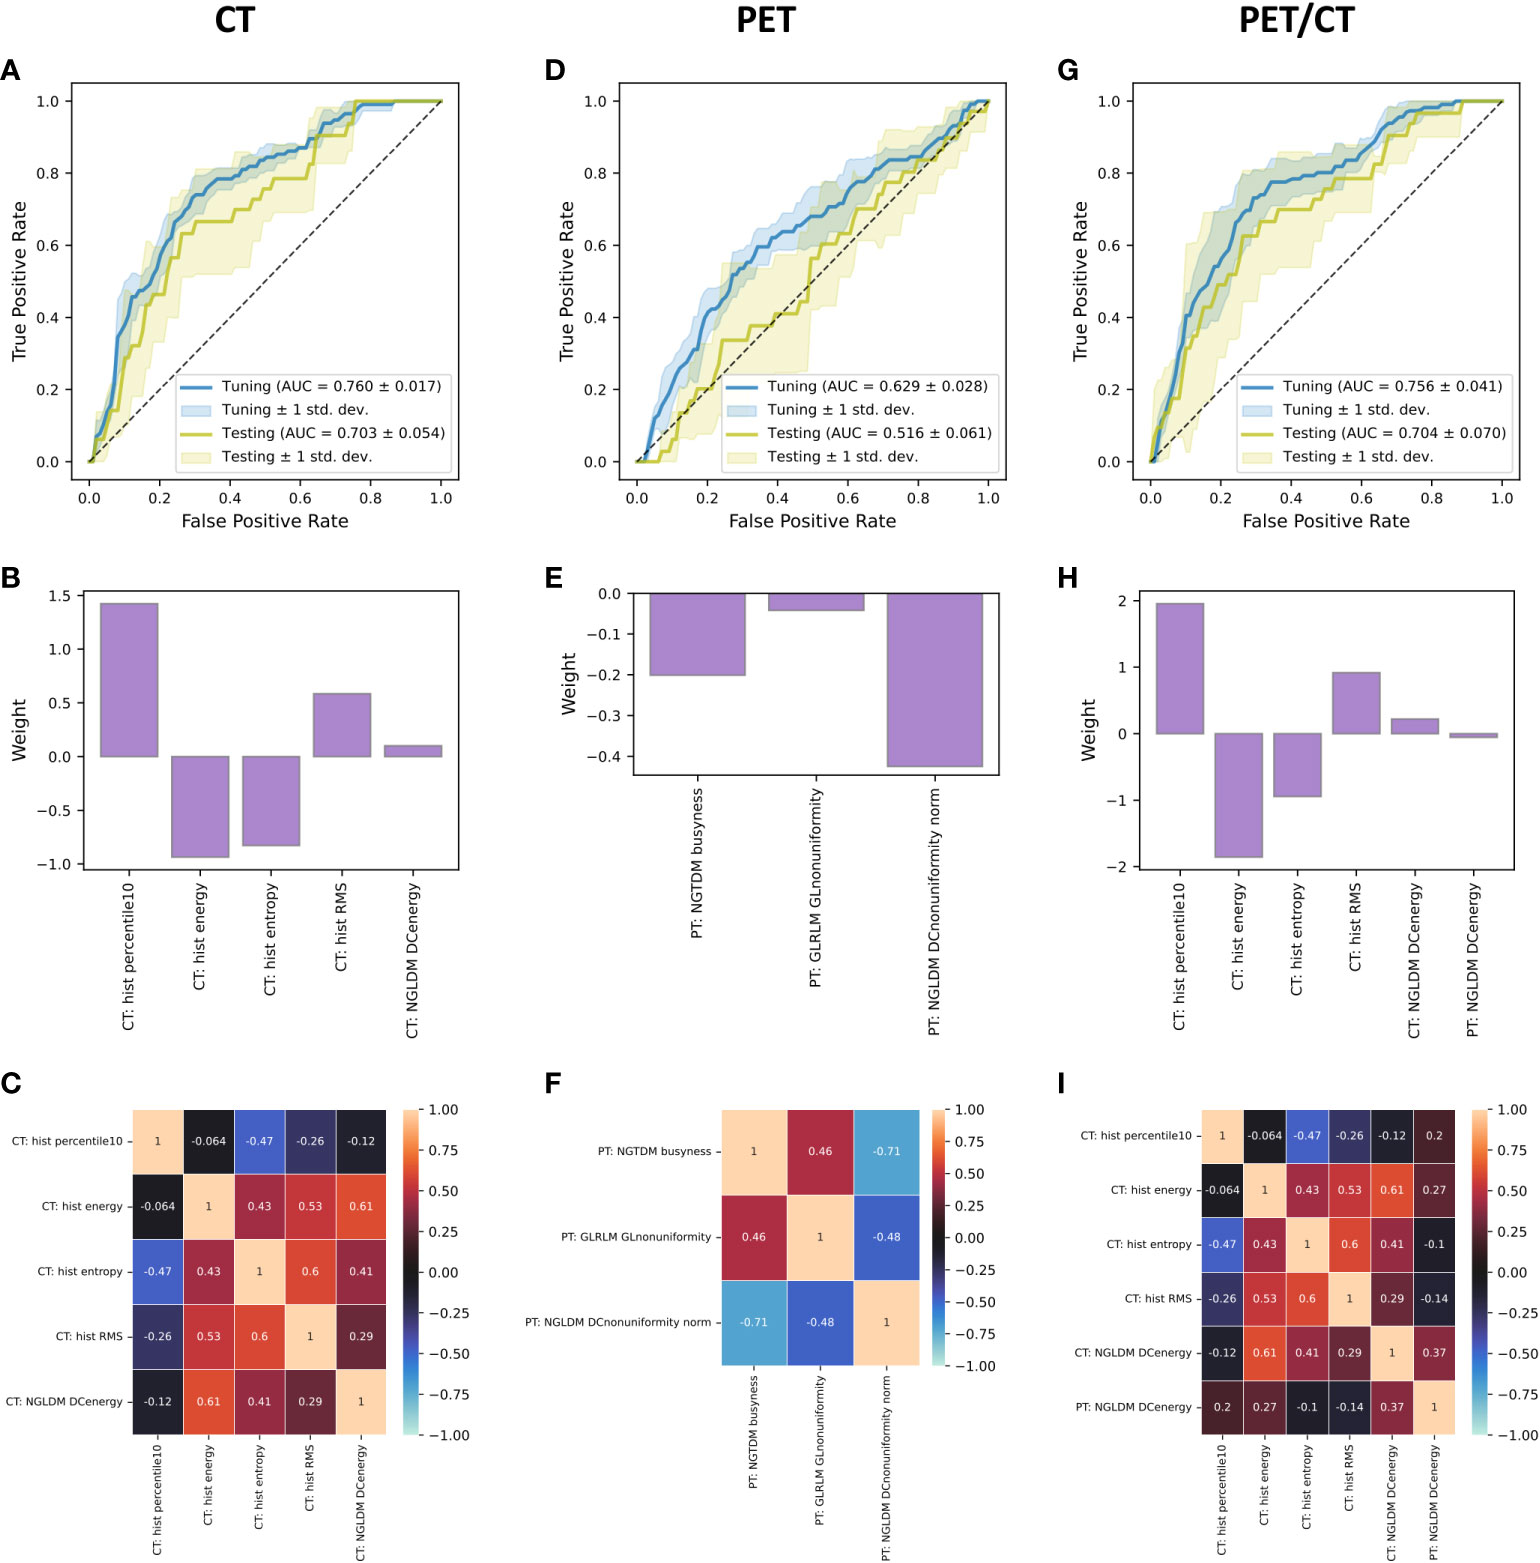

Radiomics, Tumor Volume, and Blood Biomarkers for Early Prediction of Pseudoprogression in Patients with Metastatic Melanoma Treated with Immune Checkpoint Inhibition

Immune checkpoint inhibitors (ICI) have revolutionized the treatment of patients with metastatic melanoma. However, more than 50% of patients do not respond to ICI. ICI response assessment is challenging, as novel response patterns, such as pseudoprogression (PP) are not considered in the response evaluation criteria in solid tumors (RECIST 1.1).

An increase in tumor volume could be based on either true progressive disease (TPD) or on influx of immune-competent cells (PP). Early differentiation of PP and TPD is highly relevant in daily clinical decision-making, and predictive biomarkers are needed for better patient selection. We could identify 2[18F]fluoro-2-deoxy-D-glucose–positron emission tomography/CT-based radiomic and delta-radiomic features as novel imaging markers for early differentiation of PP from TPD. In addition, we could show that the routine blood markers LDH and S100 can contribute to PP prediction.

A multimodality approach of combined radiomics and blood marker–based prediction model at an early time-point of 3 months yielded the best performance. Thereby, added toxicity or delayed treatment switch in patients with metastatic melanoma treated with ICI might be potentially avoided.

PET/CT radiomics for prediction of hyperprogression in metastatic melanoma patients treated with immune checkpoint inhibitors

This study evaluated pretreatment 2[18F]fluoro-2-deoxy-D-glucose (FDG)-PET/CT-based radiomic signatures for prediction of hyperprogression in metastatic melanoma patients treated with immune checkpoint inhibition (ICI).

Fifty-six consecutive metastatic melanoma patients treated with ICI and available imaging were included in the study and 330 metastatic lesions were individually, fully segmented on pre-treatment CT and FDG-PET imaging. Lesion hyperprogression (HPL) was defined as lesion progression according to RECIST 1.1 and doubling of tumor growth rate. Patient hyperprogression (PD-HPD) was defined as progressive disease (PD) according to RECIST 1.1 and presence of at least one HPL. Patient survival was evaluated with Kaplan-Meier curves. Mortality risk of PD-HPD status was assessed by estimation of hazard ratio (HR). Furthermore, we assessed with Fisher test and Mann-Whitney U test if demographic or treatment parameters were different between PD-HPD and the remaining patients. Pre-treatment PET/CT-based radiomic signatures were used to build models predicting HPL at three months after start of treatment. The models were internally validated with nested cross-validation. The performance metric was the area under receiver operating characteristic curve (AUC).

FDG-PET/CT-based radiomic signatures yield potential for pretreatment prediction of lesion hyperprogression, which may contribute to reducing the risk of delayed treatment adaptation in metastatic melanoma patients treated with ICI.